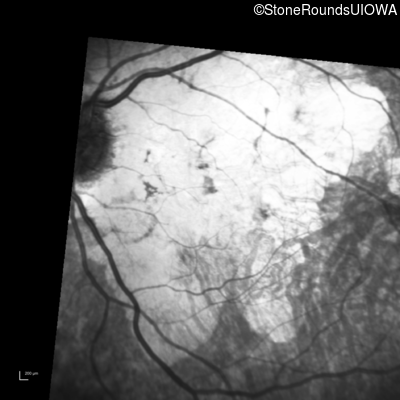

Infrared Fundus Photograph - Left - 20/200

Exemplar